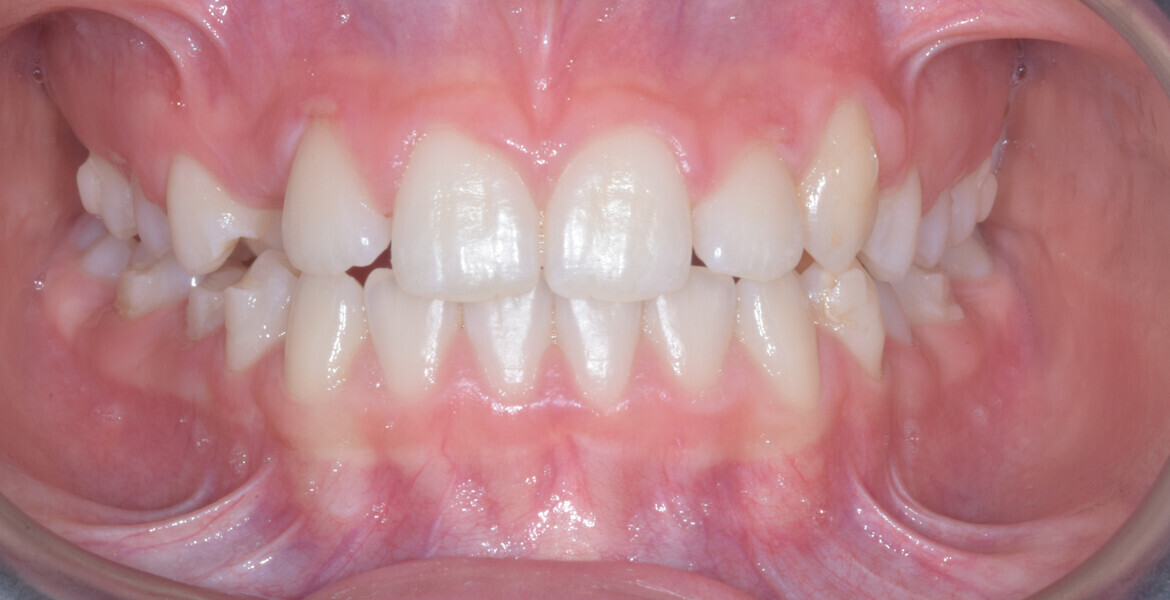

A 14-year-old female patient presented with the chief complaint of midline deviation and dental crowding in both arches. Facial analysis showed a hypodivergent growth pattern, a normal nasolabial angle, a harmonious profile and proper chin projection. Clinical examination revealed a Class III skeletal relationship (ANB = 0°) and Class I molar relationship. The maxillary right canine was absent, and this had led to space loss and mesial drift of posterior teeth on the right side, resulting in a slight Class II molar relationship. The maxillary left canine had erupted in a high position. The mandibular arch displayed crowding despite the agenesis of the right second premolar and the persistence of the primary molar (Figs. 3–11). The radiograph showed the probably premature loss of the maxillary right primary canine and consequently impacted maxillary right permanent canine, and the agenesis of the mandibular right second premolar and the mandibular right third molar (Fig. 12).

The overall treatment time was 16 months, 11 months of aligner treatment (five months initially for space creation and six months for finalisation after canine eruption) and five months of treatment with MTAs and sectional archwire. At the end of the treatment, a full Class I canine and molar relationship had been obtained, and the impacted canine had fully erupted (Figs. 34–38). A balanced smile with centered midlines had been achieved with an acceptable relationship between the maxillary incisors and lower lip, and torque control of the lateral and posterior segments had generated a broader smile. The limited movement of the upper lip on smiling detected at the beginning was stable, but the smile had improved in terms of expansion and the buccal corridor (Figs. 39–42).